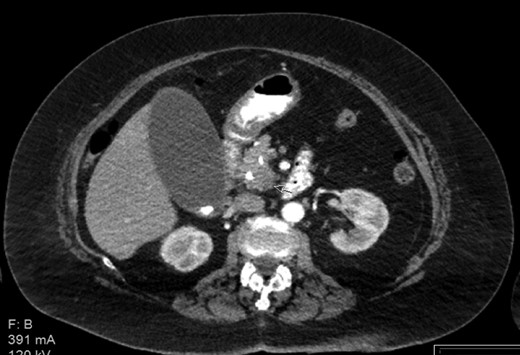

The patient is a 73-year-old elderly Caucasian woman who was initially evaluated for generalized pruritus and painless jaundice for several weeks. Past medical history was significant for Hypertension, and Obesity. Family history and social history was noncontributory. Review of systems was negative except for jaundice and pruritus. Initial laboratory workup revealed WBC 12.0 × 103/ul, Hemoglobin 12.0 g/dl, Platelets 191 × 103/ul. Liver chemistry significant for aspartate aminotransferase (AST) 104 U/l, alanine aminotransferase (ALT) 98 U/l, alkaline phosphatase (ALP) 176 U/l, total bilirubin 5.7 mg/dL and albumin 3.9 g/dL. Carbohydrate antigen 19-9 (CA 19-9) was elevated at 278 u/l. Endoscopic retrograde cholangiopancreatography (ERCP) showed distal common bile duct stricture needing a stent placement. Endoscopic ultrasound (EUS) showed 25 mm diameter pancreatic head mass. Fine needle biopsy of pancreatic head mass was suggestive of adenocarcinoma. MDCT of pancreas (Fig. 1) and liver along with PET /CT scan (Figs 2 and 3) were performed for staging, which were negative for distant metastasis. Patient underwent Whipple’s procedure. Surgical pathology was positive for poorly differentiated pancreatic ductal adenocarcinoma. Lymph nodes involving celiac axis and hepatic artery were negative for malignancy, but 6 out of 28 regional lymph nodes came positive for malignancy on pathology report. Intraoperatively liver parenchyma appeared abnormal and intraoperative ultrasound revealed early fibrosis. Random wedge biopsy from lateral segment of the liver was performed to confirm liver parenchymal disease, which interestingly came positive for 2 mm pancreatic adenocarcinoma metastatic lesion amongst fibrotic liver tissue (Fig. 4). Case was discussed in multidisciplinary conference and referred to oncology for chemotherapy. On 8 months follow up, patient maintained good performance status without any recurrence.

Contrast enhanced CT with pancreatic protocol. Pancreatic head mass.